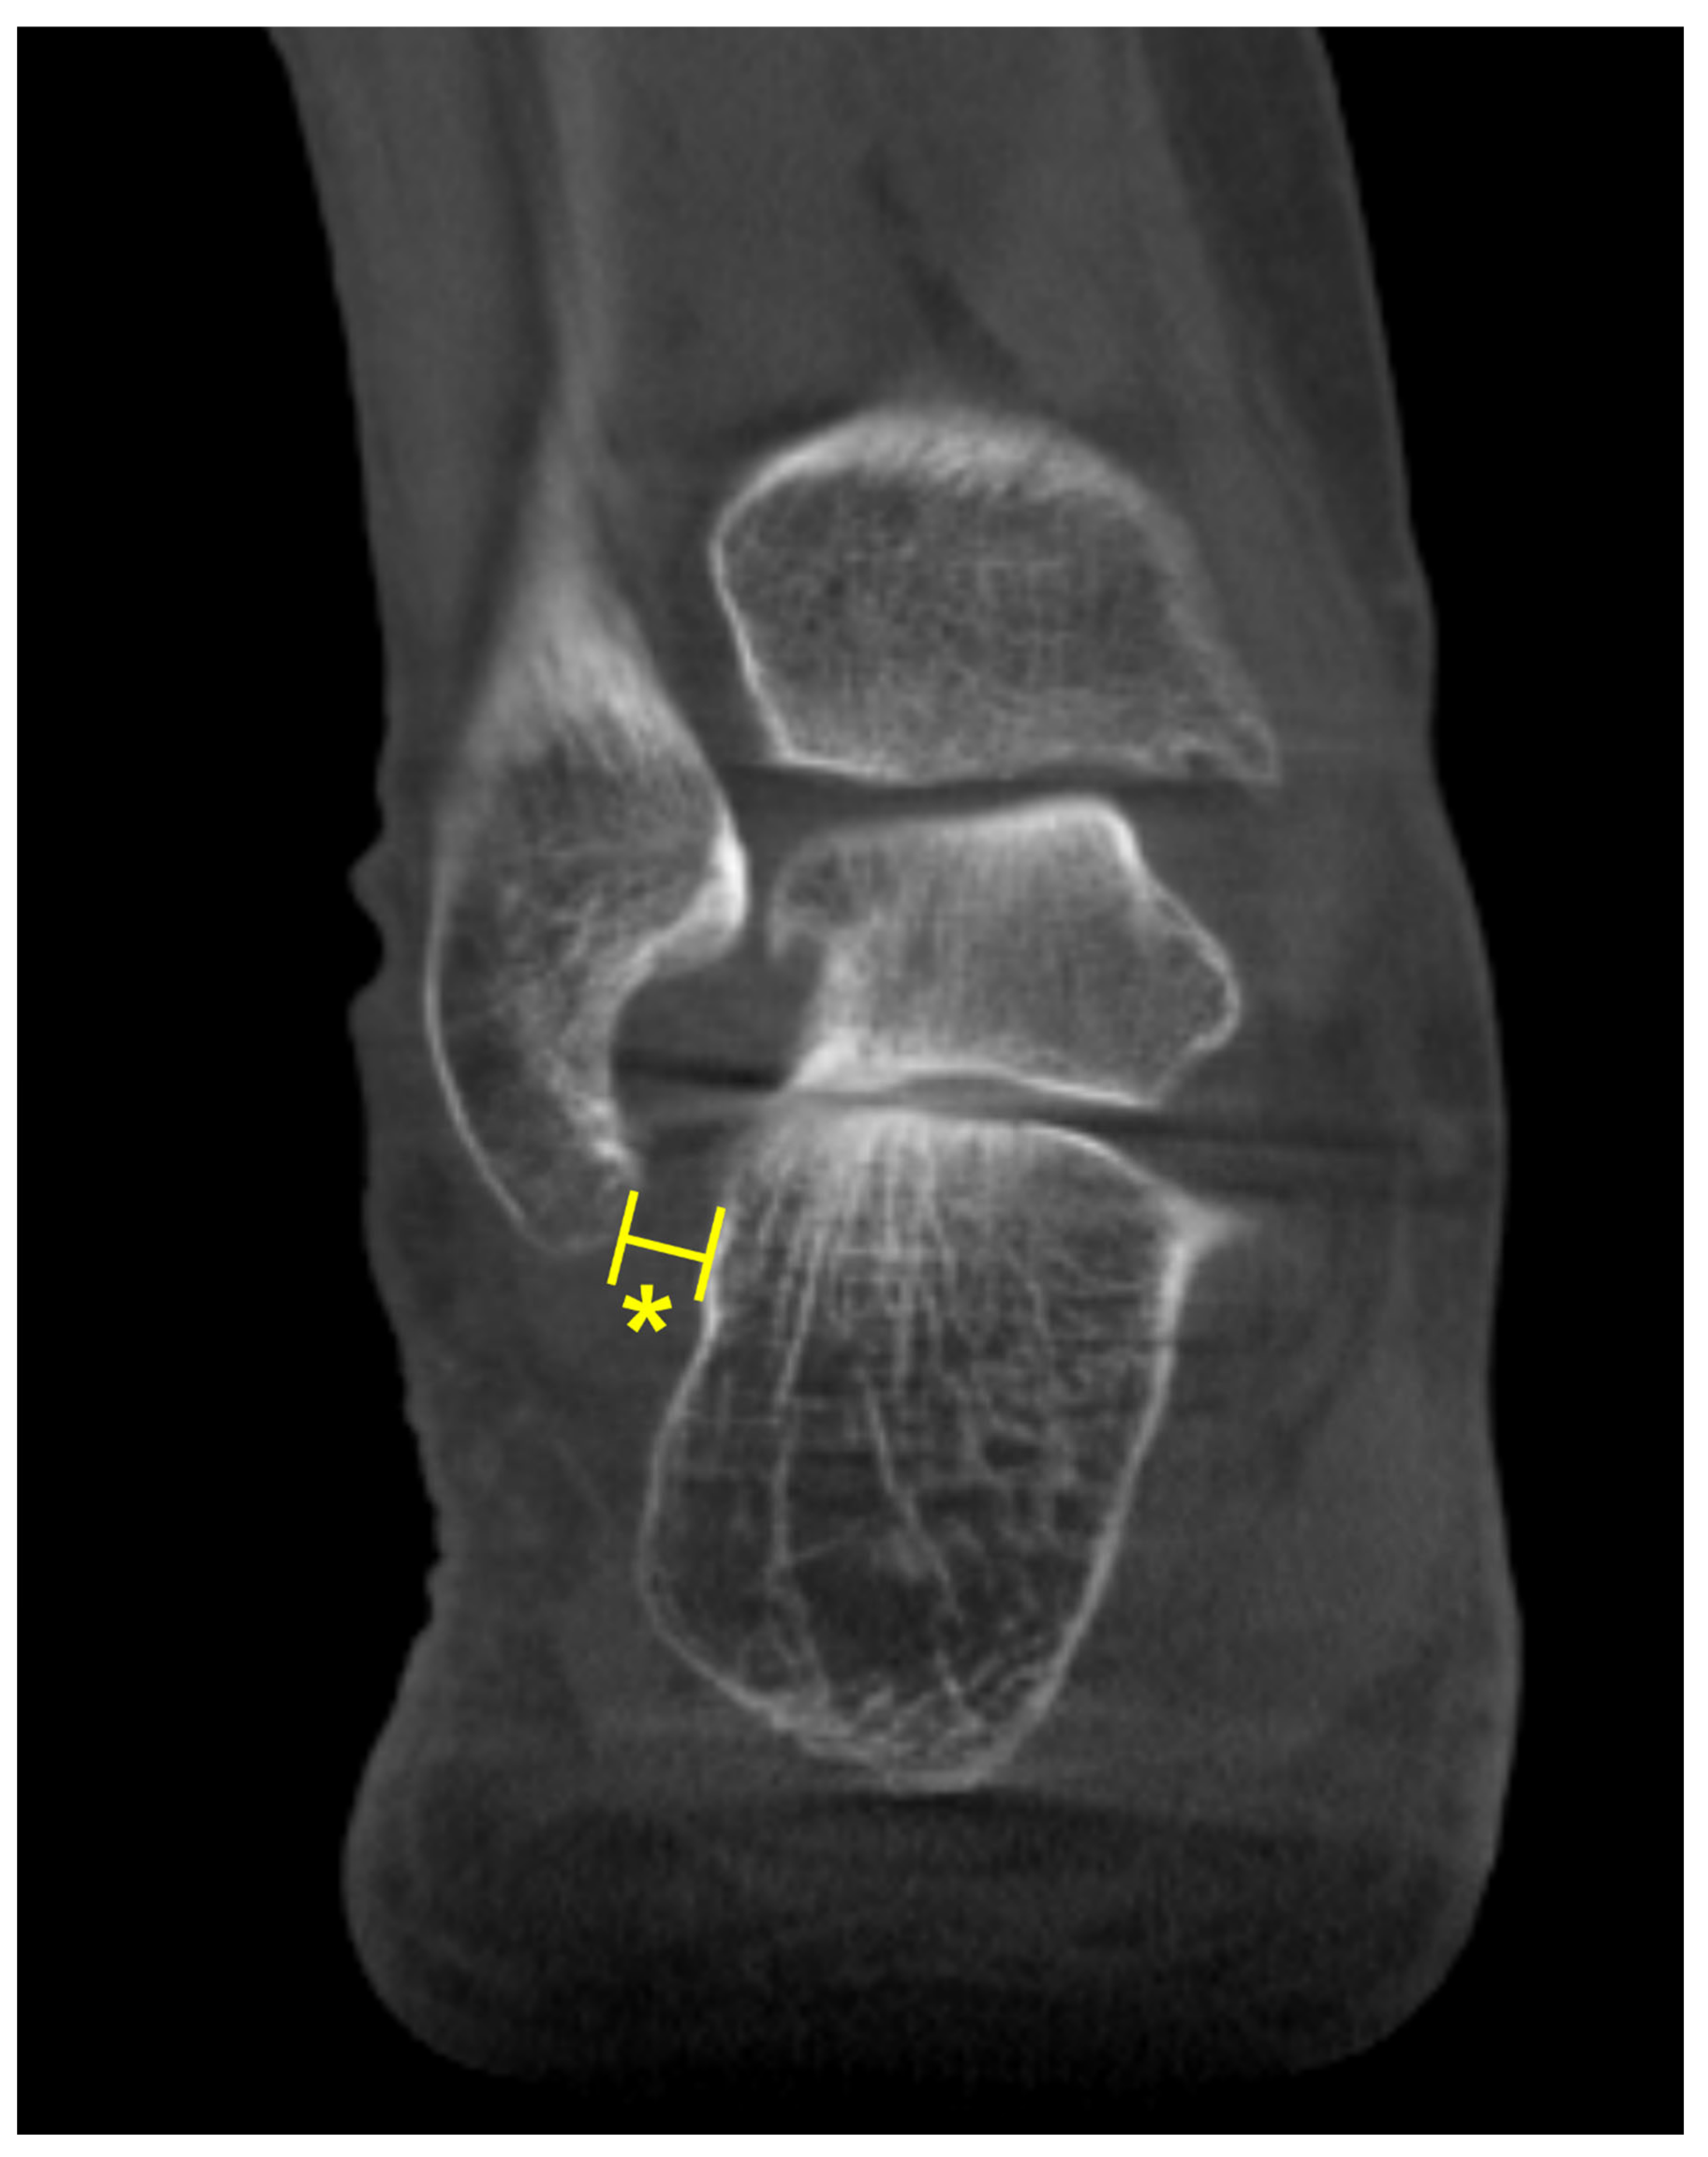

The talonavicular coverage angle is also used in WBCT as an indicator to assess midfoot abduction [34]. In fact, a new classification system for PCFD includes sinus tarsi impingement as one of the findings of midfoot abduction. Sinus tarsi impingement, which commonly causes lateral hindfoot pain, is caused by bony contact between the talus and calcaneus and should be addressed when establishing a therapeutic strategy in PCFD [40]. Because of superimposition effects, however, sinus tarsi impingement is difficult to identify using conventional radiographs. Instead, WBCT allows for identification of bony impingement in physiological standing position. Kim et al devised a novel method to measure the talocalcaneal distance, which features realignment of the coronal and sagittal planes to directly trace the inferior border of the lateral process of the talus [41] (Figure 8). The inferior border of lateral process of the talus is chosen to reconstruct the coronal reference plane because it is a constant anatomical landmark to obtain minimal talocalcaneal distance. Using this method, authors investigated correlation of talocalcaneal distance narrowing with common radiographic parameters on standard weight-bearing radiograph. They observed that talocalcaneal narrowing correlated most with talonavicular coverage, with cutoff value of 41.2 degrees. Andres et al conducted a comparative study to identify whether there is an association between WBCT-based measurements and MRI findings [42]. They found that MRI findings overestimate the presence of bony sinus tarsi impingement in approximately 42% of included population and concluded that WBCT would be a better diagnostic option to detect bony impingement in PCFD.

B. At this point, the narrowest distance between the inferior border and the calcaneal floor is measured in the selected coronal slice (Asterisk).

Figure 8. Talocalcaneal distance. A. Using the sagittal view for reference, the most inferior point of the lateral process is identified.